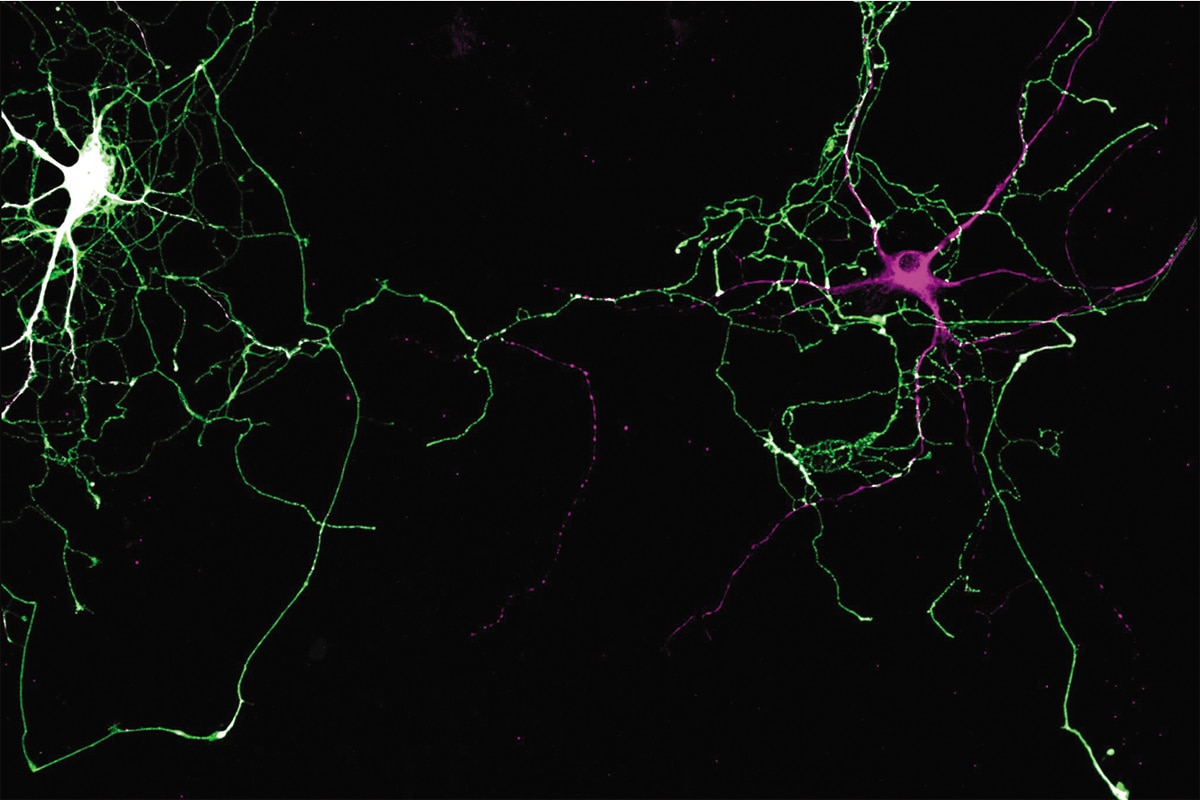

La maladie de Parkinson a pour effet de détruire les neurones dopaminergiques, qu’on peut voir ci-dessus. Image : Charles Ducrot

La maladie de Parkinson, longtemps considérée comme un problème du cerveau, serait-elle plutôt une maladie auto-immune?

Ces résidus venaient de la perte de fonction de deux gènes nommés PINK1 et Parkin, normalement en cause dans la destruction sécuritaire de la mitochondrie. Or, la dysfonction de ces gènes entraîne un autre risque : celui de développer la forme héréditaire de la maladie de Parkinson. Caractérisée par une perte progressive des neurones producteurs de dopamine, cette affection neurodégénérative touche plus de sept millions de personnes dans le monde.